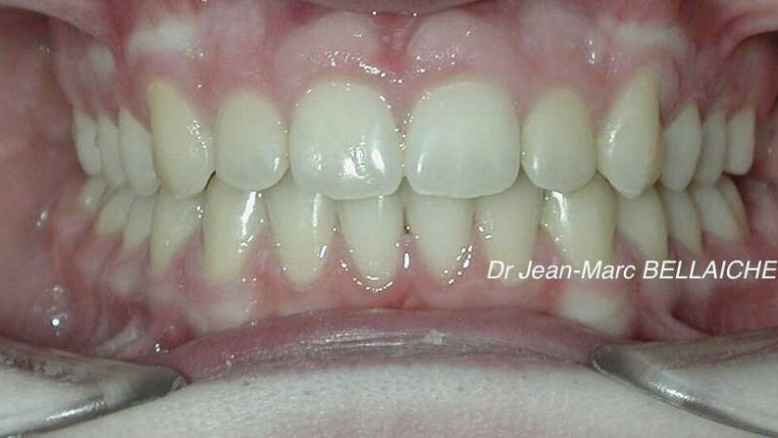

Cas 5 : Traitement orthodontique et esthétique – Cas parodontal

Situation "Avant Traitement" : Espaces entre les dents, dénivellation des hauteurs dentaires et parodontite.

Chez cette patiente adulte, l’objectif était de refermer les espaces, d’harmoniser le sourire et de compenser une perte osseuse liée à une maladie parodontale. Après stabilisation de la parodontite, le traitement orthodontique a été mené avec gouttières transparentes à forces douces, respectueuses du support osseux. Il a été complété par un blanchiment dentaire et un remodelage esthétique pour redonner au sourire équilibre et naturel.